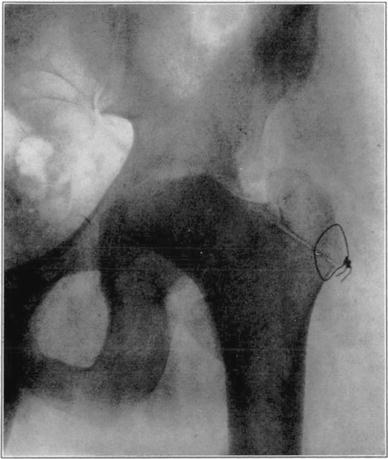

Operations which involve severence of bone or extensive separation of soft parts from bone may occasionally interfere with blood supply sufficiently to cause massive necrosis. An example of this is the necrosis of the head and neck of the femur in the following case in which arthroplasty of the hip was performed.

Case 1. Bony ankylosis following pyogenic arthritis.

Case 1. Twenty days after arthroplasty.

Case 1. Thirty-six days after arthroplasty. Beginning reduction in density in base of neck and shaft. No change in head.

Case 1. One hundred and fifty-one days after operation. Density of necrotic head unchanged but shaft and pelvis show atrophy of disuse.

Case 1. Two hundred and fifty days after operation. Head extensively reduced in density from invasion and replacement from the living bone of base of neck.

Case 1. Four hundred and four days postoperative Cavitation at base of head and further transformation.

The hip showed about forty degrees of flexion but marked limitation of abduction and rotation. Its strength had gradually improved and there was only slight discomfort in walking unless it was prolonged.

The cause for this exceptional occurrence of necrosis of head and neck without sequestration appeared to lie in the traumatism of head and denudation of neck of its covering of soft parts. However, it may have been due in part to deep-seated mild infection in the region of the new joint, despite the absence of discharge from that region. Failure of the necrotic head to be sequestrated speaks decidedly in favor of aseptic instead of septic necrosis although sequestration may not occur in the presence of mild infection of a necrotic area. In another case I observed necrosis of the head and neck following an arthroplasty in which there was infection of the wound with a purulent discharge, but the dead bone was sequestrated in the course of several weeks. In the case here reported functional stimulation of the bones resulting from movement of the joint, combined with protection of the necrotic head from weight-bearing, was followed by creeping substitution of the necrotic bone by new bone in the greater part of the head without either erosion of dead bone or the development of marked deformity.